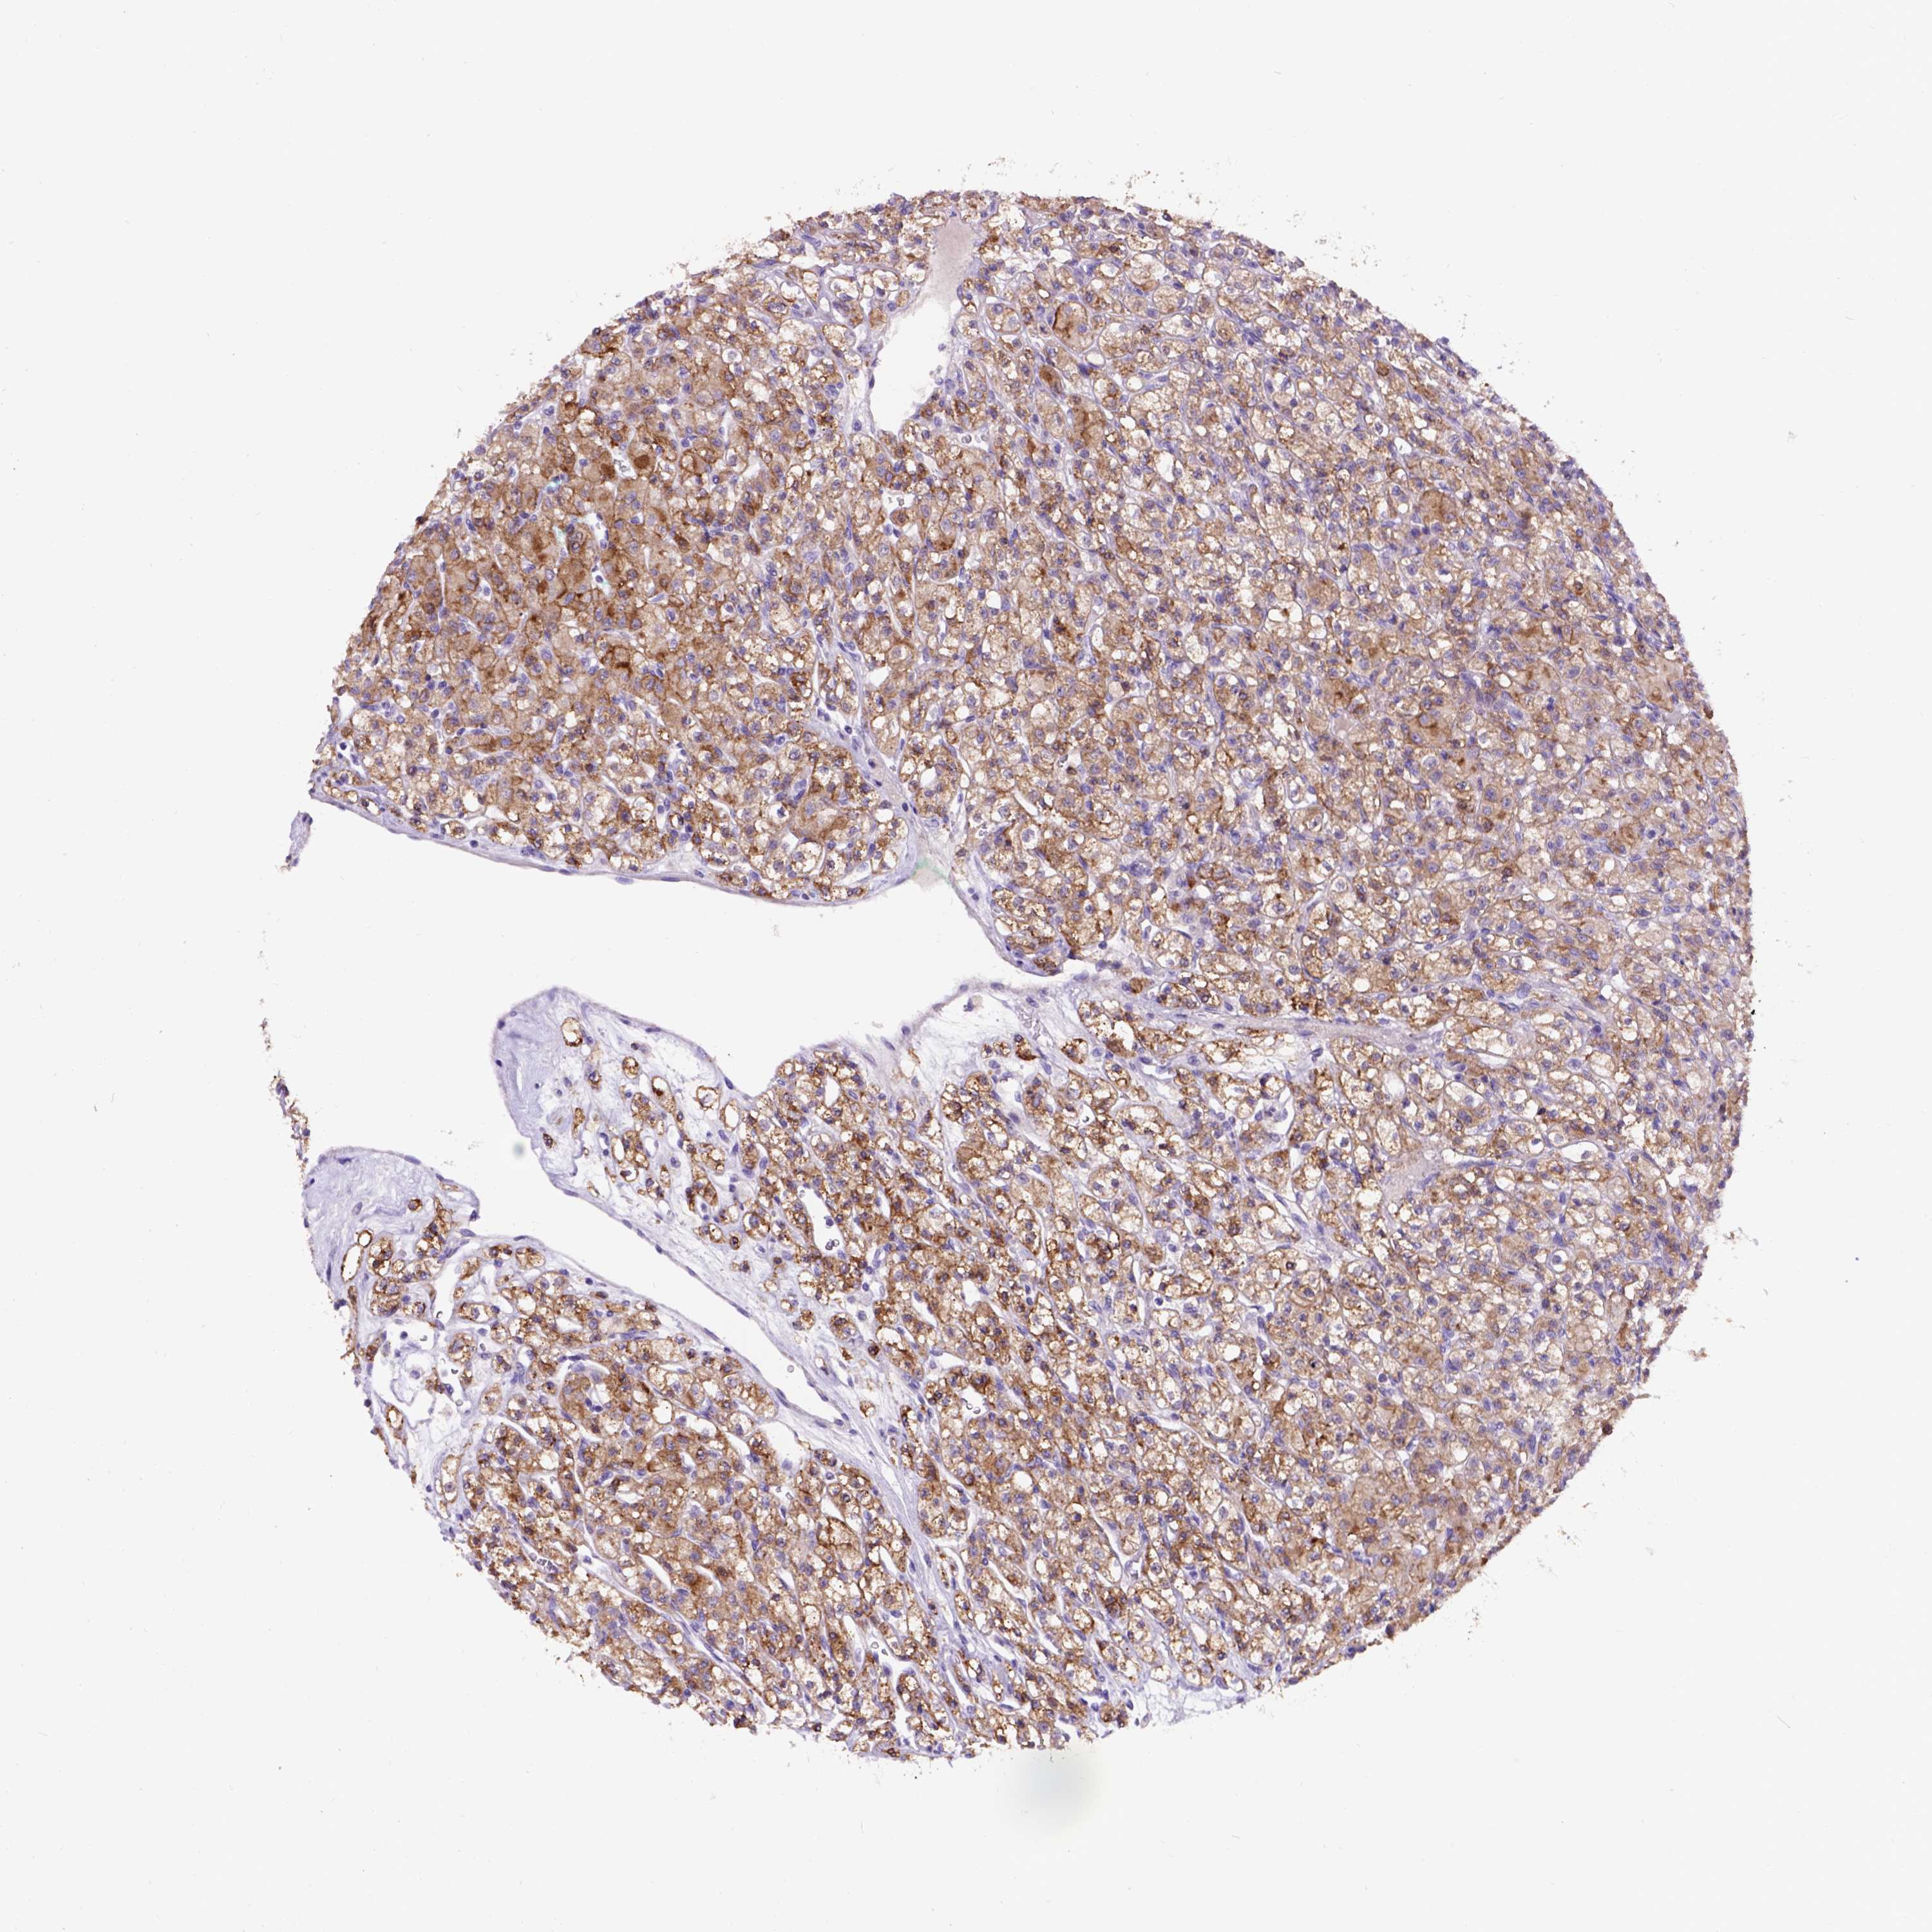

CANCER RENAL CANCER Show tissue menu

KICH TCGA KIRC TCGA KIRC VALIDATION KIRP TCGA PROTEIN RCC CPTAC PROTEIN EXPRESSION

Average pTPM 52.9

Number of samples 521